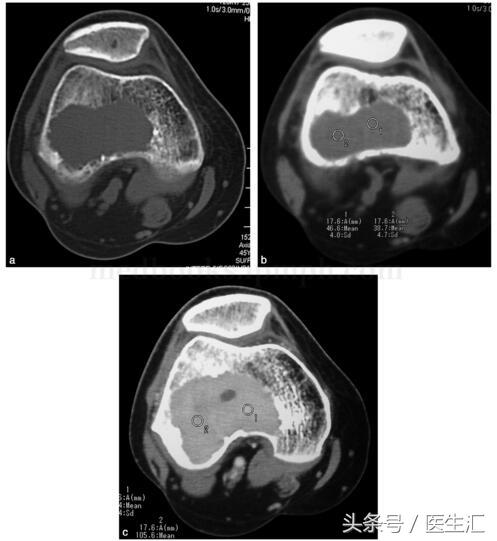

影像學(xué)檢查:X 線示右股骨遠(yuǎn)端骨端發(fā)生的一個(gè)偏心、基質(zhì)均勻、皮質(zhì)膨脹、皮質(zhì)無(wú)骨破壞、無(wú)骨膜反應(yīng)、無(wú)軟組織腫塊的溶骨性破壞(圖29‐1a,圖29‐1b)。CT 示右股骨遠(yuǎn)端骨端的溶骨性破壞,基質(zhì)均勻,注射造影劑后,病變強(qiáng)化,CT 值由強(qiáng)化前的40HU 增加到強(qiáng)化后的110HU(圖29‐2a~圖29‐2c)。

圖29‐2

a﹒CT 橫斷面示股骨外髁處溶骨性骨破壞(骨窗);

b﹒CT 橫斷面示股骨外髁處溶骨性破壞,CT 值為46HU(軟組織窗);

c﹒CT 橫斷面示增強(qiáng)CT 示腫瘤強(qiáng)化,CT 值達(dá)105HU

在與正常骨交界處,可有篩孔樣改變。CT 掃描可提供病變更加的細(xì)節(jié),病變組織的CT 值在40HU 左右,造影增強(qiáng)后,病灶可被的強(qiáng)化,甚至可達(dá)100HU 左右。MRI 可清楚地發(fā)現(xiàn)腫物在髓腔內(nèi)的范圍,當(dāng)病變合并有動(dòng)脈瘤樣骨囊腫時(shí),MRI 可清楚地發(fā)現(xiàn)液‐液平面。如大部分骨腫瘤一樣,骨巨細(xì)胞瘤在T 1加權(quán)像上,表現(xiàn)為低至中等信號(hào)強(qiáng)度,在T 2加權(quán)像上表現(xiàn)為高信號(hào)。腫瘤的髓外部分在T 2加權(quán)像上顯示佳。在骨掃描上,可發(fā)現(xiàn)多發(fā)的病灶。約有49%的患者可有炸面包圈樣的改變,即腫瘤的周?chē)糠治蘸怂貪舛雀?,而中心部位吸收相?duì)較少。